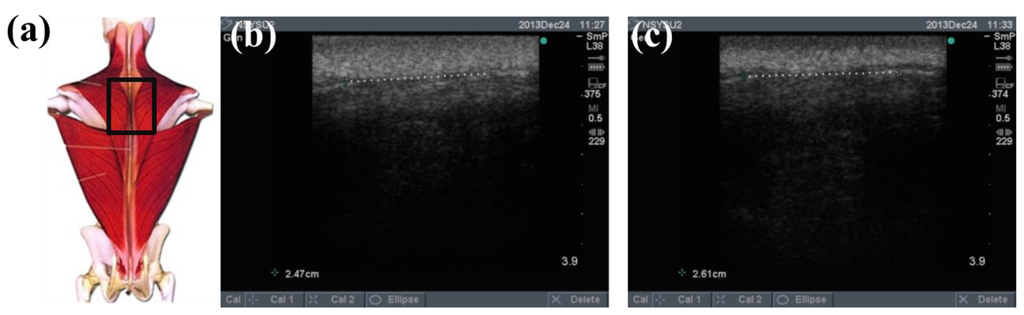

To determine the feasibility of the training system proposed in this study, we used ultrasound imaging to observe the muscles' length changes during contraction and determined whether these changes were correlated with skin stretches. Ultrasound image measurement is used for exploring the human body, such as observing tissue structure, blood or tissue movement, and the mechanical characteristics of tissues. Tissue structure is mainly observed using grayscale images. The primary principle in ultrasound imaging is the reflection of ultrasound waves when the waves encounter different density interfaces in the human body. The piezoelectric crystals in the sensor head receives the signals and converts the signals into images according to the direction, distance, and strength of the waves. Ultrasound imaging is often used to examine tumours, tissues, or organs inside the body. Moreover, ultrasound images are also usually used to exam the muscle and soft tissue in rehabilitation and orthopaedic departments [12–16]. The SonoSite Titan ultrasound system (FUJIFILM SonoSite, Inc, Bothell, WA, USA) was used to measure the muscle length changes during exercise. The trapezius, mid erector spinae, and lower erector spinae were measured. The ultrasound image of the muscles at different trunk angles during Roman chair back hyperextension training is shown in Figures 10, 11 and 12, the (b) component showed the image in the preparatory actions and (c) component showed the image in the flexion 45 degrees. The muscle length in the specific positions is shown in Table 6. The lower erector spinae shown in Table 6 had a muscle shortening length of 0.53 cm (the largest length change). The test position correspond to skin stretch of 20%–35%, as shown in Figure 3b, was the largest change among the three positions. The results showed that during Roman chair back hyperextension training, changes in back skeletal muscle extension length exhibited a positive correlation changes in skin stretch. Therefore, the feasibility of a proof of concept sensor has been demonstrated.

| Trapezius Back Skeletal Muscle Extension Length (cm) | Mid Erector Spinae Extension Length (cm) | Lower Erector Spinae Extension Length (cm) | |

|---|---|---|---|

| Preparatory action | 2.47 | 2.94 | 2.94 |

| Anteflexion | 2.61 | 3.17 | 2.41 |

| Corresponding skin stretch | 0%–3% | 3%–12% | 20%–35% |